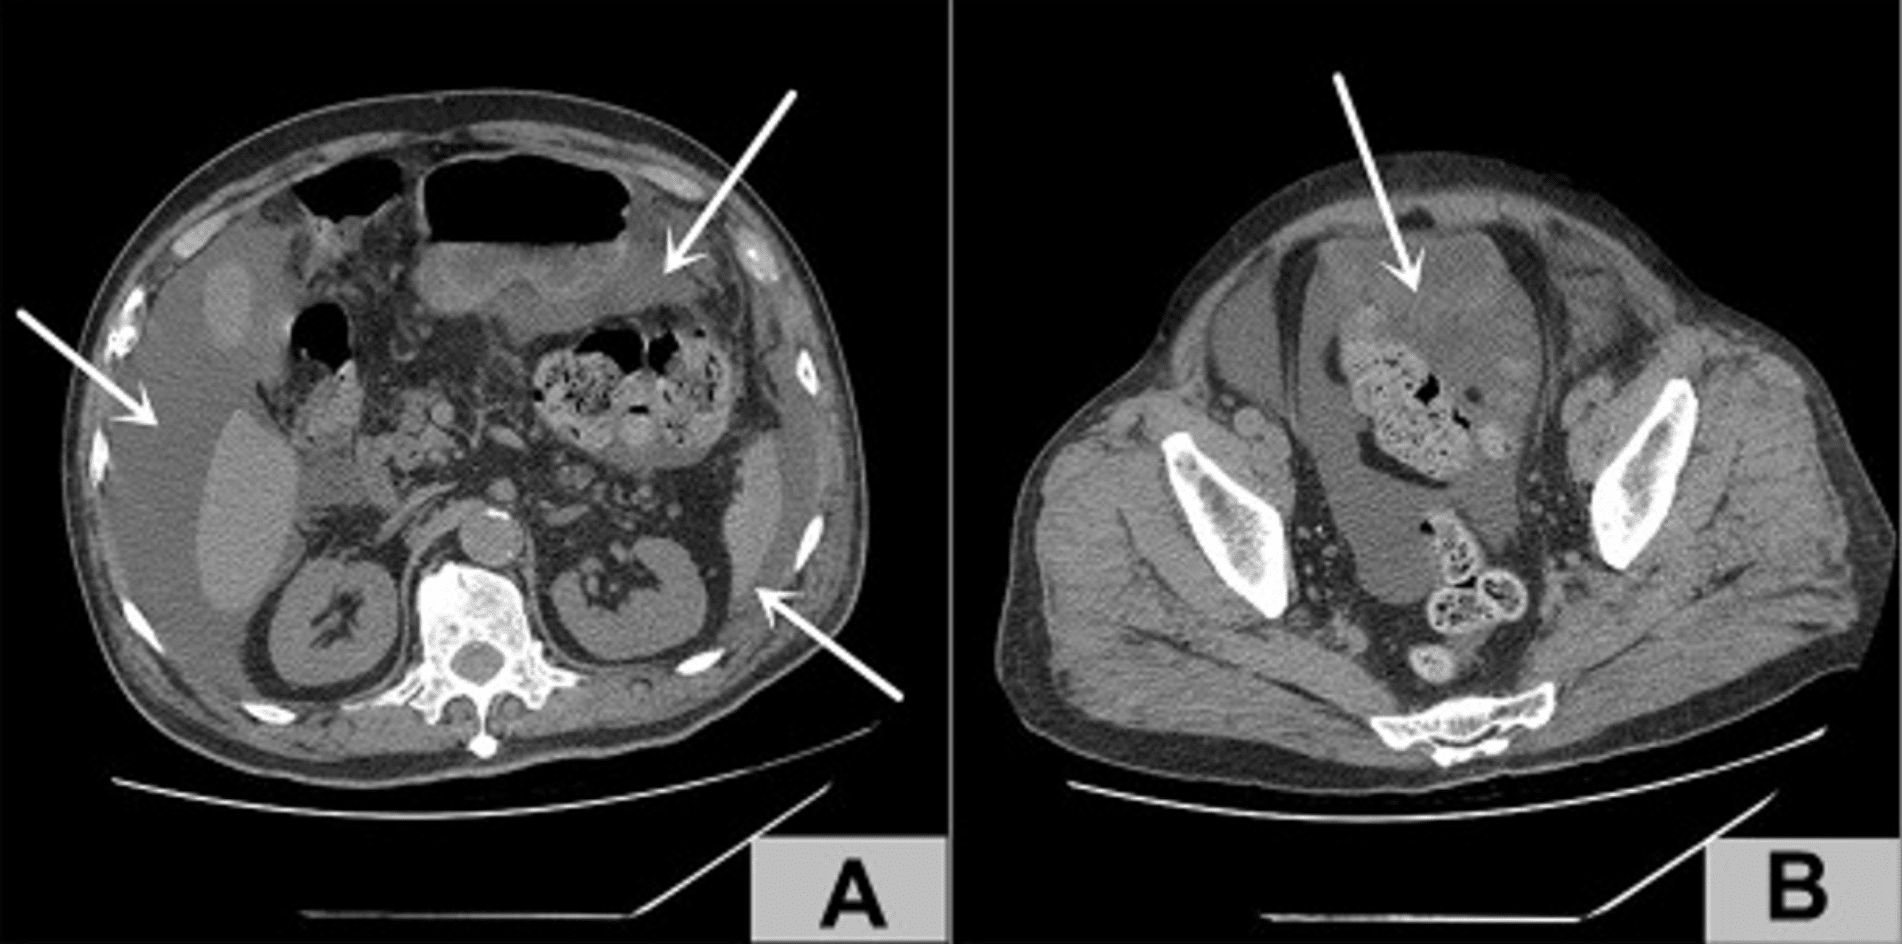

Image 2 : Dans la section A de l’image, les flèches blanches indiquent l’accumulation de liquide dans l’abdomen. Dans la partie B de l’image, la flèche blanche indique l’endroit où la rupture de la vessie a été suspectée.1

Des examens complémentaires ont révélé une ascite massive : une quantité importante de liquide dans la région de l’abdomen et du bassin a été visualisée par tomodensitométrie abdominale. Le côlon était fortement distendu.